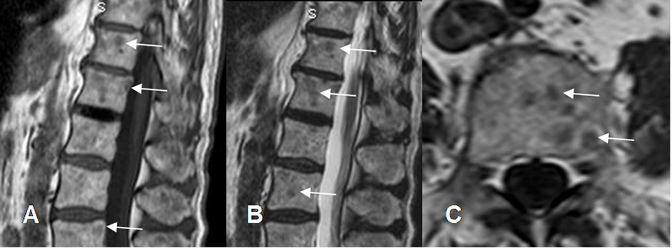

Fig 231. Micrometástasis.

A: RM sagital en T1, B: RM sagital en T2 y C: RM axial en T1. Múltiples imágenes hipointensas en ambas secuencias,

menores de 1 cm, en un paciente con neo de próstata, por micrometástasis.